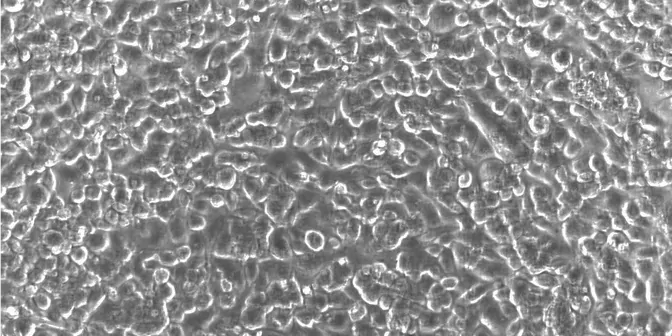

With live-cell imaging, researchers can overcome this limitation. Live-cell imaging uses microscopy to visualize ACT dynamics over time. Researchers can examine activity over hours to weeks and capture all critical time points without any guesswork.

But when it comes to testing ACTs, live-cell imaging presents its own challenges. For example, researchers first plate target cells and then place their effector cells on top, potentially obscuring the view and making it difficult to accurately measure cytotoxicity. Researchers can thus use dyes to distinguish between the two cell layers, but this extra step can sometimes disturb the activity of the effector cells and disrupt the results. Finally, given the subjectivity inherent in analyzing visual data, monitoring cells for signs of cell death requires a trained eye.